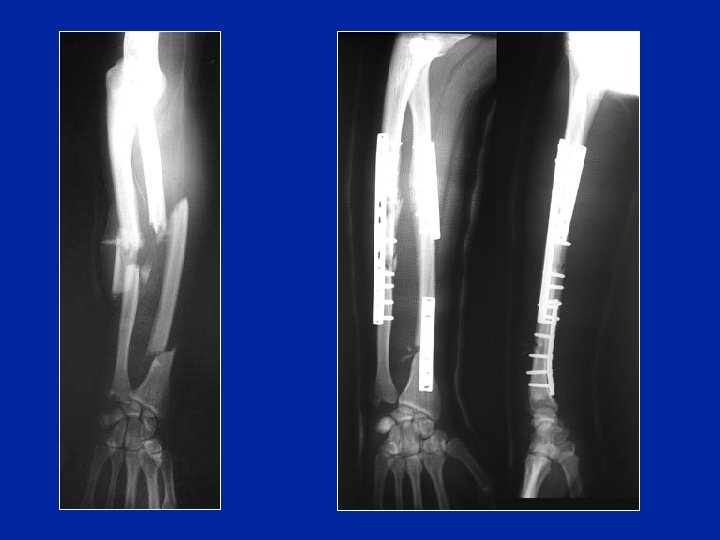

Tratamiento quirúrgico Fracturas irreductibles del niño Fracturas desplazadas del adulto Movilización precoz Consolidación en 3 meses

Desplazamiento Osteosíntesis por medio de placas y tornillos